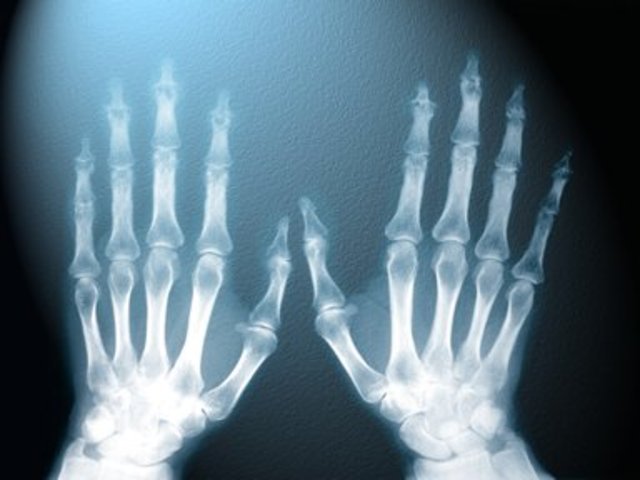

• X-rays were first discovered in 1895

X-rays were first discovered in 1895

X-rays were first discovered in 1895 when, during experiments with electric currents passed through a vacuum tube, Wilhelm Conrad Röntgen noted that a nearby fluorescent screen glowed when the current was being passed. When the current was switched off the screen stopped glowing. He attributed this effect to previously unknown rays which, X being the symbol for an unknown quantity, he called X-rays.